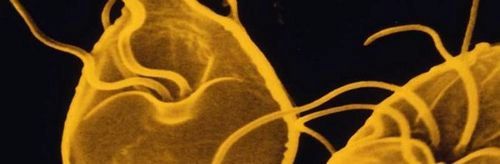

Лямблії в кишечнику

Лямблії відносяться до класу джгутикових, представляють грушоподібної форми з вісьмома відгалуженнями у вигляді джгутиків, мають присоски, за допомогою якої вони кріпляться до стінок кишки. Цисти харчуються частинками їжі потрапила в стравохід, що дає можливість мікроорганізмам розмножуватися з великою швидкістю шляхом розподілу.